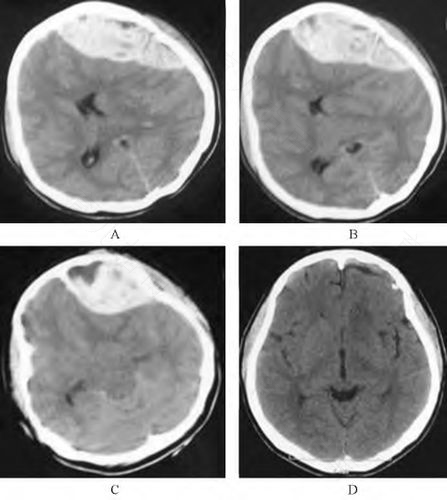

严重的头部外伤也会因为皮质血管的伤害,而形成巨大的硬脑膜下血肿,且常并发严重脑挫伤、脑内血肿和脑水肿。婴儿的硬脑膜下血肿,除有血块或血水外,也常合并硬脑膜下积水。